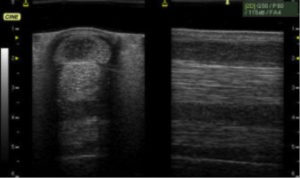

Until recently technology has been disappointing. While ultrasound, which is most commonly suggested and used, has been available from the early 80’s, even the best ultrasounds are limited in the type of information they relay. At the end we are looking at integrity differences represented in grayscale, which is very vague, and only of a limited area of the tendon at one time. Ultrasound is also very operator sensitive – in other words, different technicians/vets will often get different images and therefore differing information. This makes sharing information and carrying out reliable follow-up scans to monitor progress almost impossible to do accurately.

Traditional ultrasound on the top, compared to the detailed imaging provided by the UTC